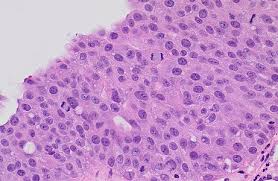

Urothelial carcinoma

the urothelial or transitional character of cells of urothelial carcinoma include the presence of longitudinal nuclear grooves that are often appreciable usually only in low-grade tumors, but are absent to only focally present in high-grade tumors.